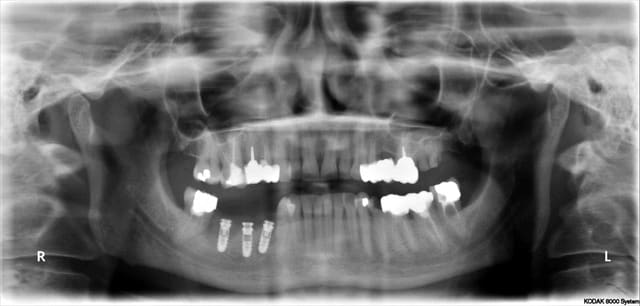

Le cas de ce matin, cela montre que même avec une planif et un guide c'est le temps opératoire qui décide

j'ai bêtement cassé la table vesti de la 45 lors de l'exo

par sécurité je suis allé chercher un meilleur ancrage en distal,

Donc le guide ne fait pas tout!!!